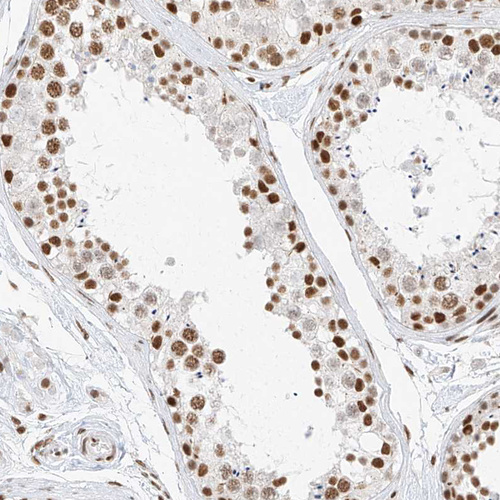

Immunohistochemical staining of human testis shows strong nuclear positivity in cells in seminiferous ducts.